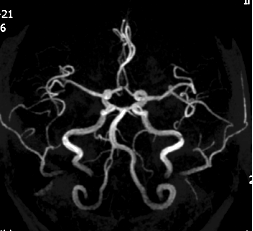

一 颅脑疾病:对脑血管疾病(脑梗死、出血、动静脉畸形、动脉瘤等)、脑肿瘤、炎性病变、脑白质病变、退行性病变及先天畸形具有明确优势。

六 心脏和大血管:心脏电影和磁共振血管成像可用于先天性心脏病、心肌疾病、心包疾病和心脏大血管病变的诊断。

MRA示右基底动脉开窗 DWI示急性脑梗死